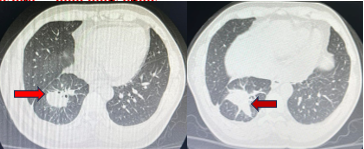

Chụp cắt lớp vi tính lồng ngực 1/10/2019 (sau điều trị)

Hình 4:Hình ảnh khối u thùy dưới phổi Phải giảm kích thước đáng kể sau điều trị (mũi tên)